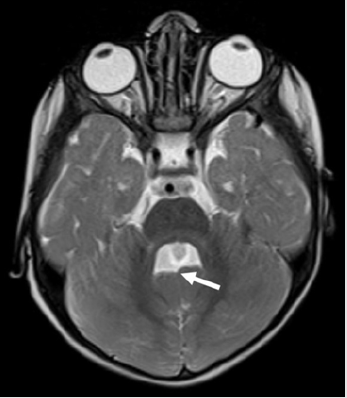

A 1-year-old boy presented to the Paediatrics department of our Institute with global developmental delay and extrapyramidal features. He was a term child born out of consanguineous marriage with an uneventful birth and family history. On examination, the infant was found to have nystagmus. No other ocular anomalies were present. No polydactyly or oro-facial defects were visualized. The patient was referred for MRI examination of brain in our Radiology Department which was carried out under sedation in Siemens Magnetom Aera 1.5 T MRI scanner. Axial MRI sections of brain revealed the characteristic “Molar Tooth” appearance of midbrain (Figure 1) with “Batwing Shaped” fourth ventricle. The cerebellar vermis was severely hypoplastic, dysmorphic and clefted (Figure 2). Sagittal MRI sections of brain showed small dysmorphic vermis with an elongated fourth ventricle. The roof of the fourth ventricle was convex upwards with an “enlarged rounded fastigial point”. Note was made of enlarged retro cerebellar space (Figure 3).

Figure 2: Axial T2WI MRI section of brain of the infant with Joubert Syndrome showing “Batwing” appearance of the fourth ventricle with small and clefted cerebellar vermis (arrow).

MRI is the primary imaging modality for diagnosis of Joubert Syndrome. “Molar tooth sign” is a mandatory and classical imaging feature seen on axial sections of brain. It is attributed to the malformation of midbrain and hindbrain where elongation and thickening of the superior cerebellar peduncles is seen along with a deep inter-peduncular fossa [1–3, 5]. Absence of decussation of fibres of superior cerebellar peduncles is the cause of deep interpeduncular fossa of mid brain. Using diffusion tensor imaging, this has been well illustrated via fibre tracking by Poretti et al [6]. Functional MRI has provided complementary information by recording abnormal activation patterns of brainstem nuclei. The other significant imaging feature of the disease includes “Clefted Vermis” with a “batwing Appearance” of Fourth ventricle. Midline sagittal sections of MRI show a small vermis which is dysmorphic with a deformed forth ventricle. The fourth ventricle is elongated, shows upward convexity of its roof and an enlarged rounded fastigium. Our case showed all these classical features of Joubert Syndrome on MRI imaging.Additional infratentorial manifestations include enlargement of the posterior cranial fossa, increased retrocerebellar CSF space along with hypoplastic as well as dysplastic cerebellar hemispheres.